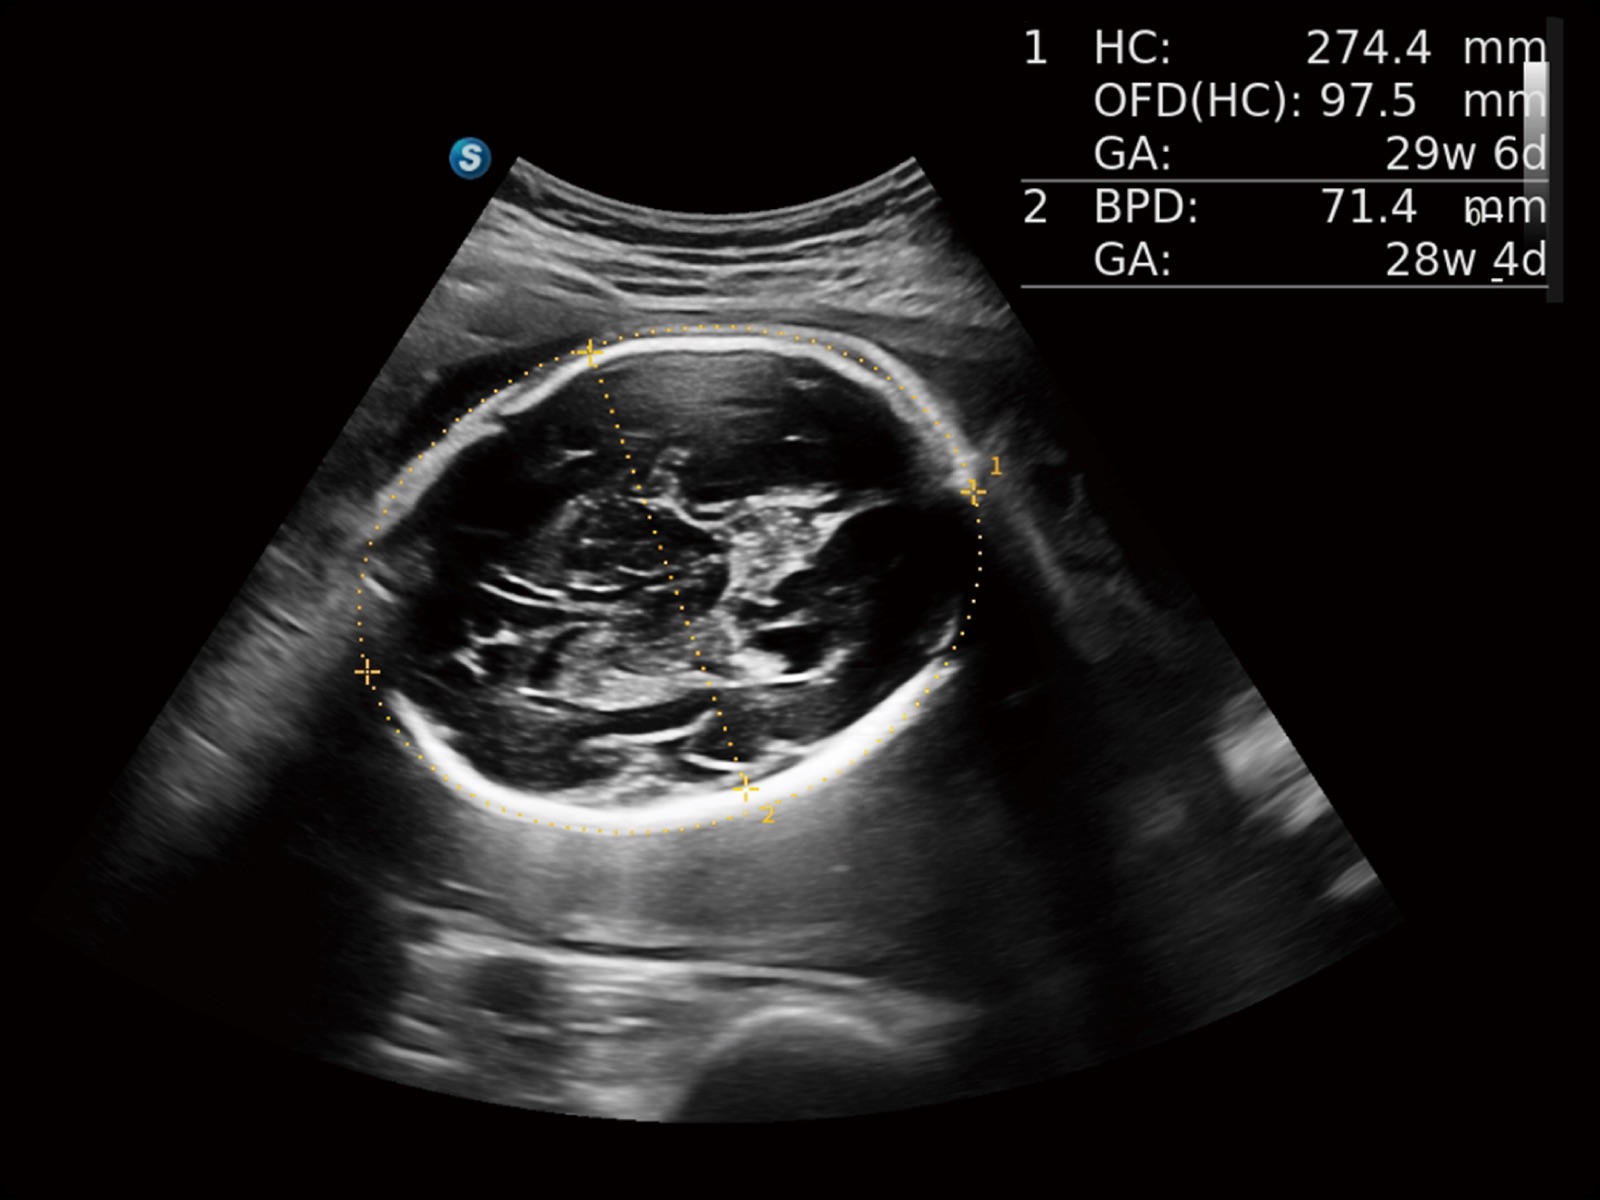

妇产应用